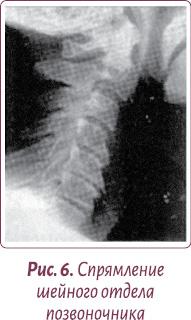

Бывает, наоборот, шейный изгиб излишне спрямляется (рис. 6).